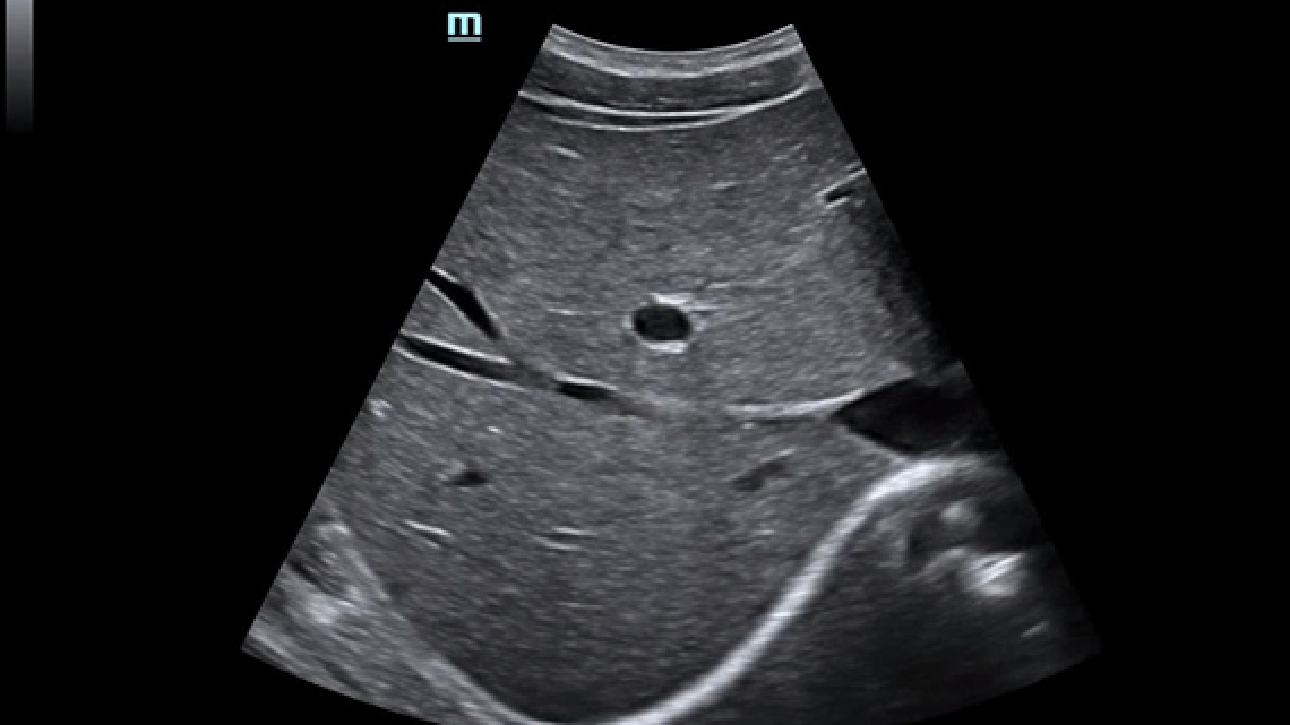

Clinical Images